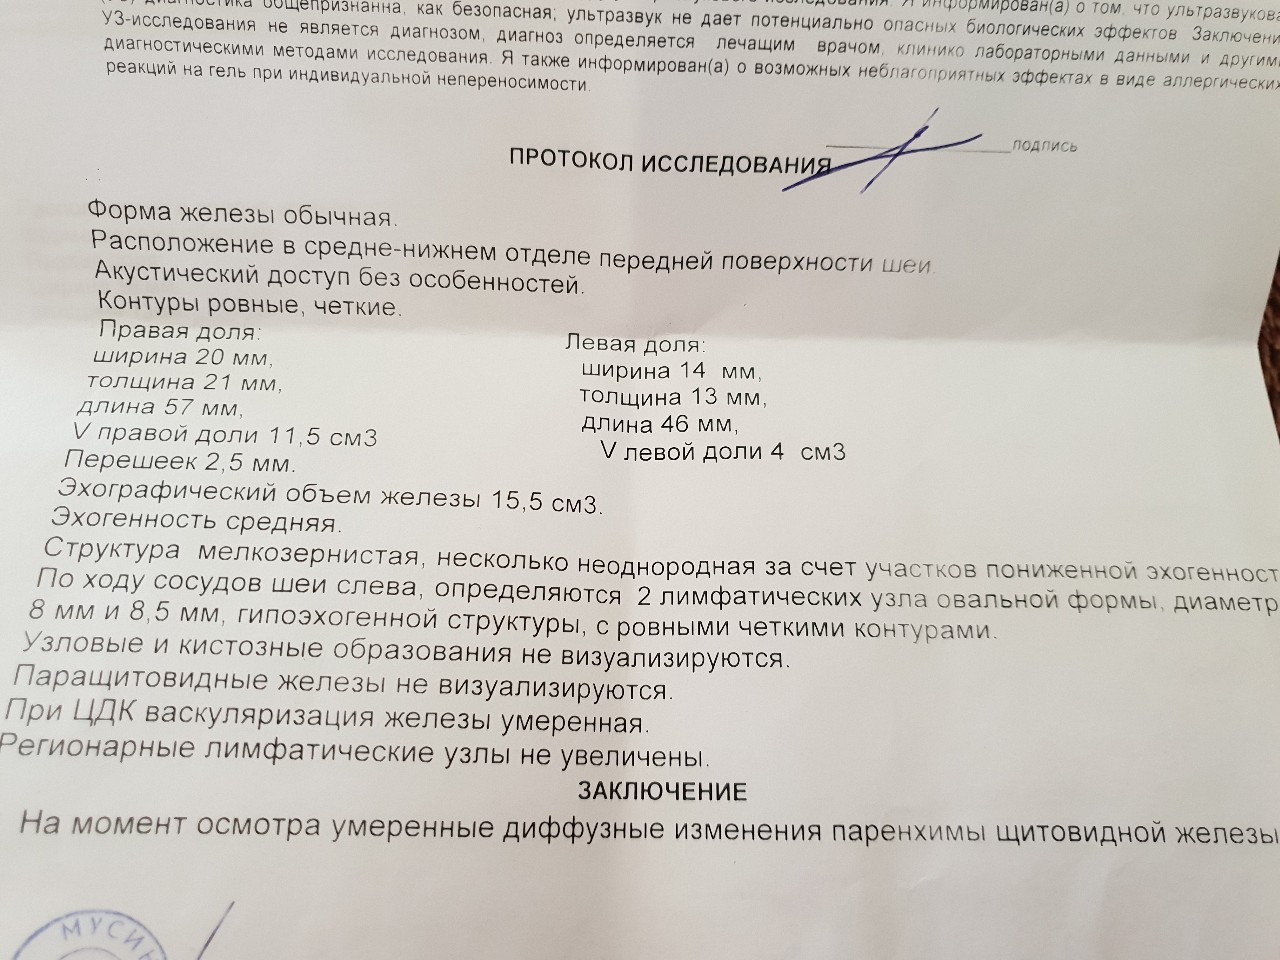

Особенности и диагностика левостороннего кровотока